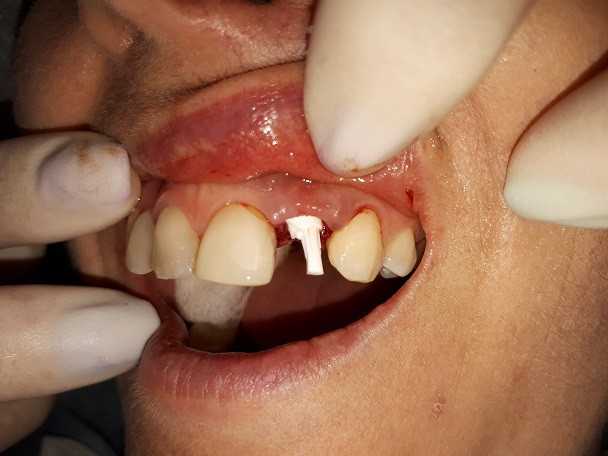

Жалобы: на отсутствие зубов, неудовлетворительную эстетику зубных рядов, невозможность жевать, снижение высоты прикуса. Что сделано: удаление зубов на в/ч и н/ч, установка имплантатов Bredent Sky и одномоментное протезирование акриловыми протезами с опорой на имплантаты по протоколу Fast & Fixed (зубы за один день). Через 8 месяцев проведена работа по замене протезов на постоянные металлокерамические. Что получил пациент: красивые и ровные зубные ряды, возможность нормально питаться с первого дня после операции, поднята высота прикуса, теперь не стесняется улыбаться.